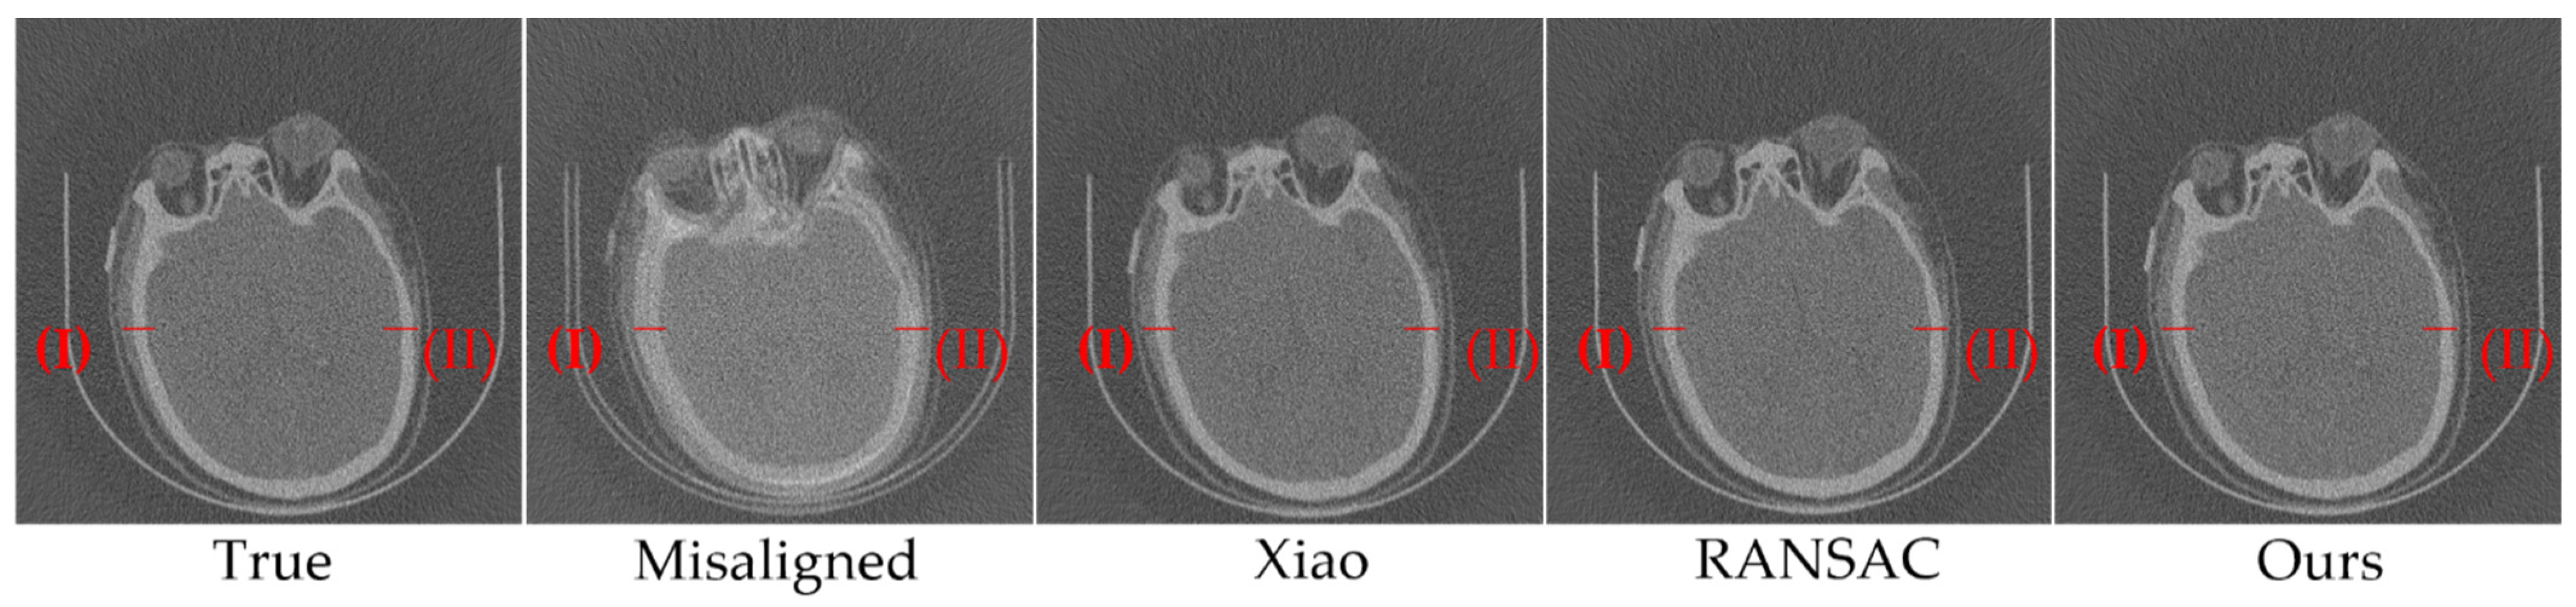

3.1. Simulation Experiments

3.2. Nanotomography Experimental Section

| Truth parameters | 255.000 | 2.000 |

| Parameters Calculated by Xiao | 255.000 | 2.137 |

| Parameters Calculate by RANSAC | 255.012 | 1.951 |

| Parameters Calculated by our method | 254.997 | 1.995 |